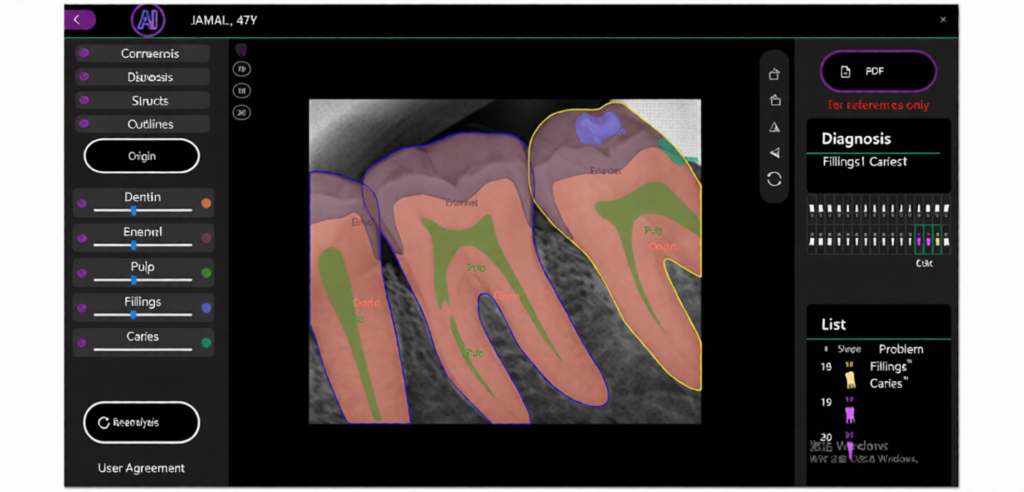

1. AI-Enhanced Imaging Technology

This Professional Dental Digital X-Ray Sensor AI-Enhanced uses advanced imaging technology to produce clear, detailed images. AI-enhanced processing helps improve image sharpness and diagnostic precision.

2. High-Resolution Dental Imaging

The Dental X-Ray sensor provides high-resolution imaging that allows dentists to examine teeth, roots, gums, and jaw structure more effectively.

Quick Diagnosis

AI-enhanced imaging supports dentists in identifying issues faster.

Improved Diagnostic Confidence

Clear and detailed imaging helps dentists make accurate decisions.